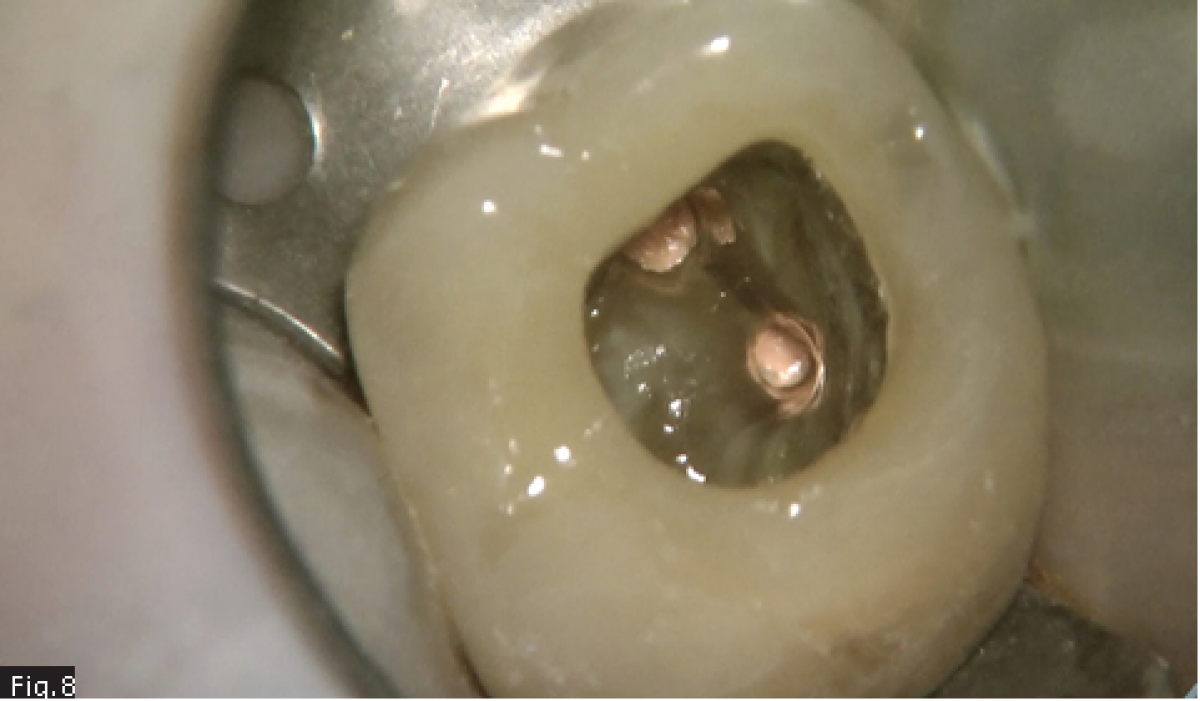

Considering the presence of an endodontic lesion and swelling, a lot of time was dedicated to decontamination of the root canal system (Fig. 5) (18). The device chosen to deliver the irrigating solution right to the working length was IrriFlex (Produits Dentaires SA, Switzerland) (Fig. 6) because, thanks to its flexibility, it was able to deliver the irrigant to the apical third of each root, without any effort, without stopping in case of curvatures. The irrigant was then activated by means of ultrasonic inserts (19) according to the indications given by Tonini et al. (12). After ensuring that the root canals were dry, they were filled according to the warm gutta percha compaction technique (Fig. 8-10). After that, the access cavity was filled by means of a direct composite restoration (Fig. 11) and a post operative x-ray was taken in order to check the final result (Fig. 12).